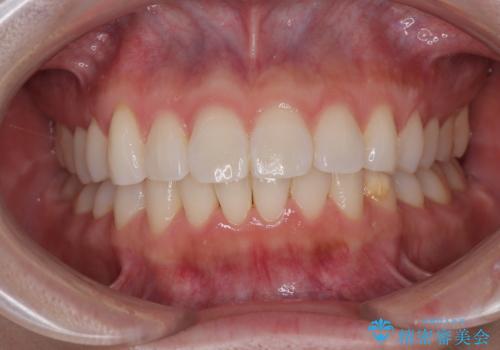

気になる前歯を短期間で治す インビザライン・モデレートでの矯正治療

インビザライン・モデレートは、製作できるアライナーの枚数に制限があるため、移動可能な量に限りがあるものの、インビザライン・ライトよりも枚数が多いため、幅広い症例に対応可能です。